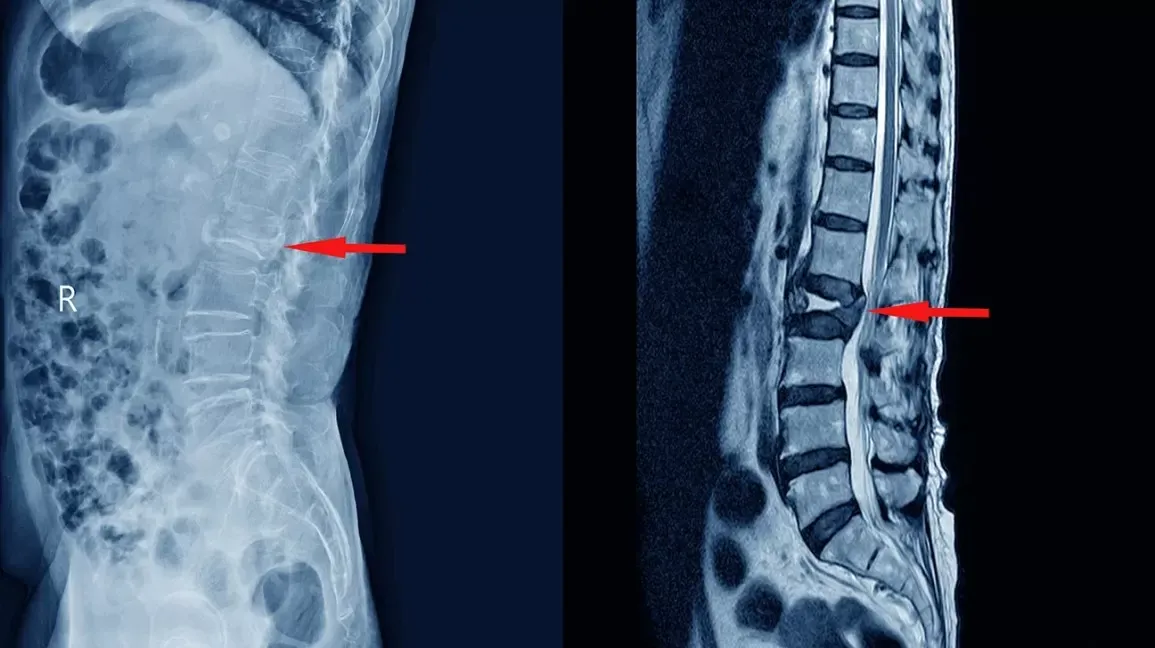

Why MRI Alone Cannot Diagnose Back Pain

Here’s a fact that changes how you should approach finding a spine surgeon: an MRI is a picture of anatomy, not a diagnosis of pain. That distinction matters more than most patients realize.

Every person over 45 walking around without any back pain has disc abnormalities that would show up on imaging. Disc bulges, herniations, degenerative changes – all visible on MRI, all completely asymptomatic in most people.

Of those disc herniations, only 10% to 15% actually cause pain. The other 85% to 90% are incidental findings – anatomical changes unrelated to the patient’s symptoms.

An MRI cannot tell you which disc herniation is causing pain and which is incidental. It can’t identify inflammation in the posterior annular fibers. It can’t show which of multiple potential pain generators is creating symptoms. It can’t distinguish between nerve compression that causes leg pain and annular tears that cause back pain.

Yet most physicians look at an MRI, see a disc herniation, and conclude that’s the source of pain. That approach fails for most patients with chronic back pain, because the actual pain generator isn’t the disc herniation itself – it’s the tear in the posterior annulus where that herniation is stuck, causing chronic inflammation.

Standard MRI imaging doesn’t clearly show annular tears. They appear as subtle changes in signal intensity that radiologists describe as “disc degeneration.” The actual tear causing pain goes unrecognized.